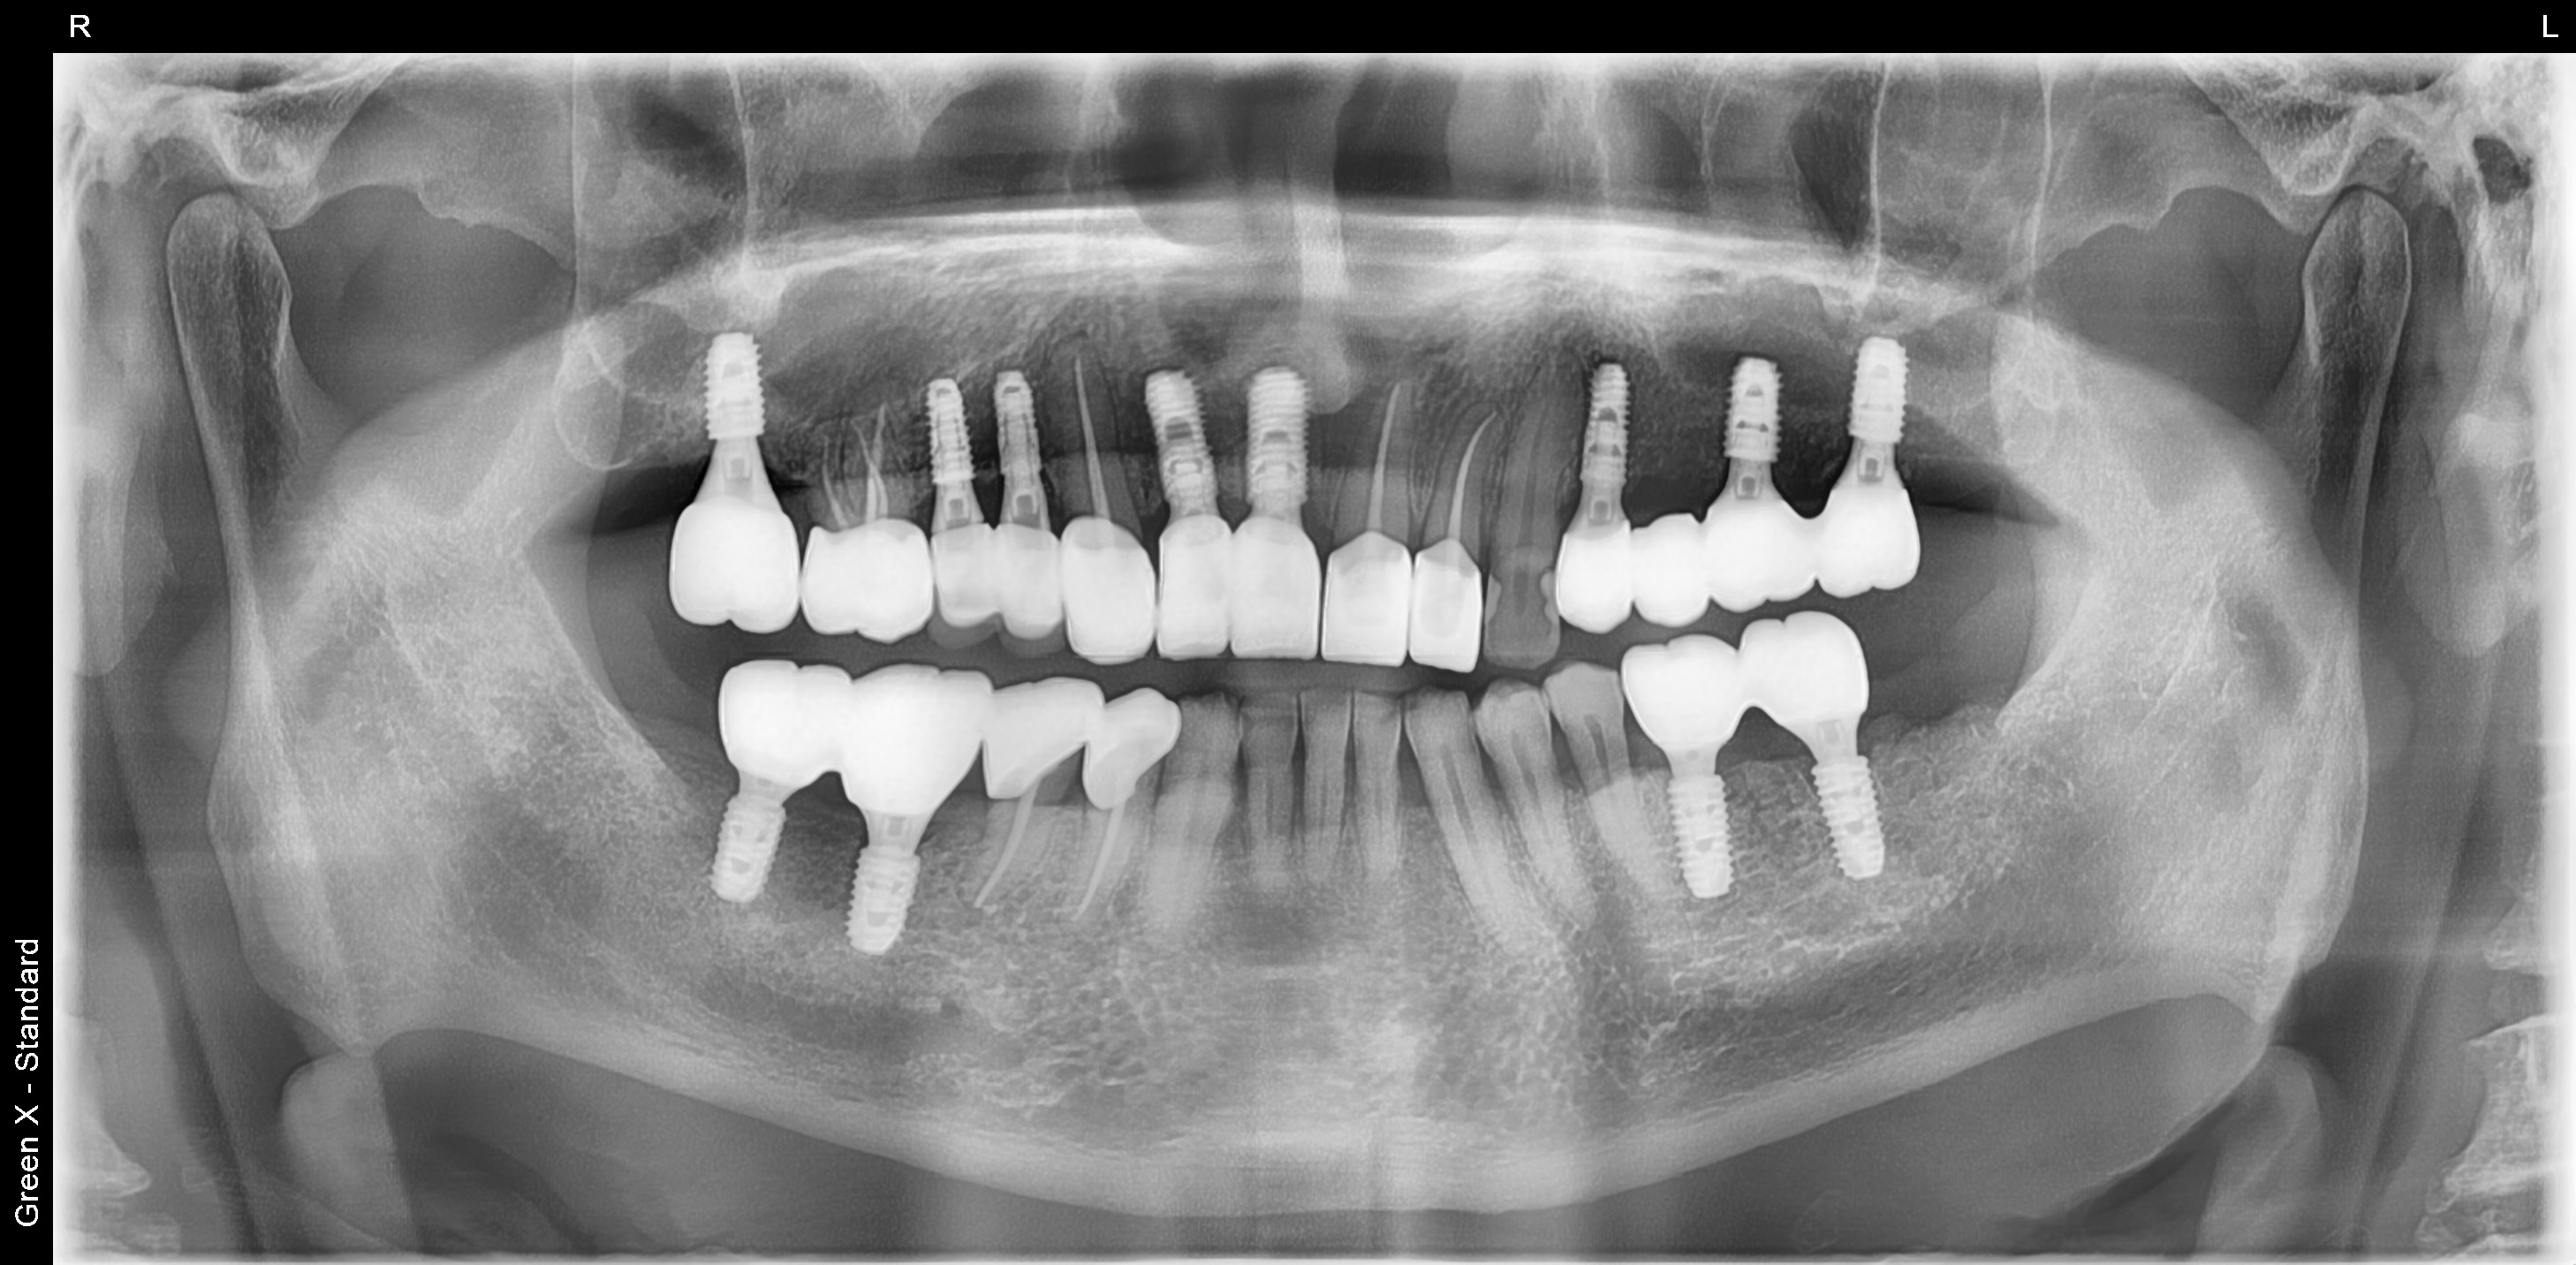

풍무동 서울케이치과에 처음 내원시 충치가 심해서 뿌리만 남은 어금니가 대부분인 상태여서, 식사가 어려웠던 분이었습니다.

어금니 부위 10개 임플란트, 앞니 2개 임플란트를 식립하여 전체 치아를 재건해드린 사례입니다.

<임플란트 치료 후>